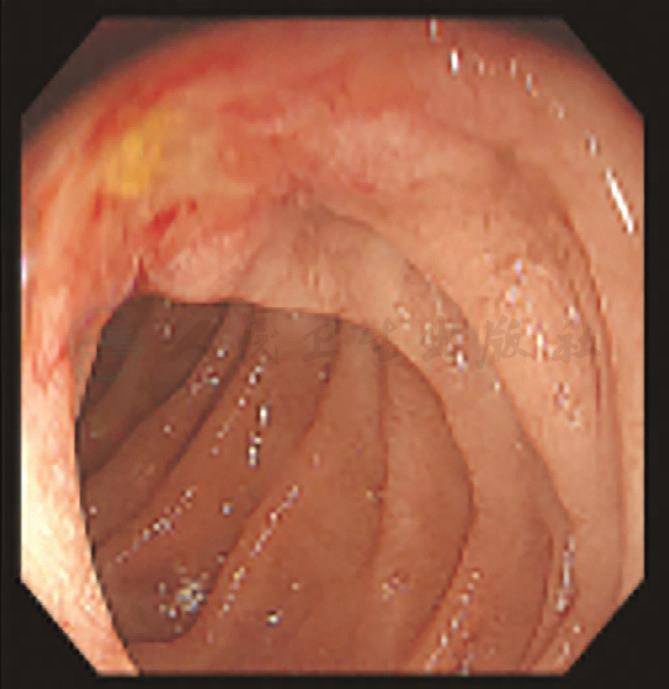

考虑贫血严重,全身情况较差,入院后给予补液扩容改善贫血等支持治疗,血红蛋白纠正至74g/L。第3天:患者排黑便数次,量1 000mL左右,急查血红蛋白53g/L。初步诊断急性消化道出血,首选早期胃镜检查。数字减影血管造影(digital subtraction angiography,DSA)与CTA检查同样具有较好的诊断价值,结合该患者具有十二指肠乳头占位,肿瘤合并出血的可能性较大。因此,首先选择了急诊胃镜检查,发现十二指肠乳头处有隆起占位性病变,局部黏膜粗糙,并有持续少量渗血(图4)。为控制出血,我们继而选择了数字减影血管造影(DSA)栓塞胃十二指肠动脉(gastroduodenal artery,GDA)止血(图5)。DSA术后1周,患者出血停止,血红蛋白逐渐上升至71g/L。

图4 急诊胃镜见乳头占位伴渗血

患者入院第3天出血急性失血后,由于无呕血,放置的胃管内亦未见到血性液体,仅为黑便。医师的第一反应是做DSA检查,寻找下消化道出血的部位。但基于该患者有壶腹周围占位的情况,从“一元论”的角度,“直觉”为该部位出血,急诊内镜的阳性表现证实了猜测。